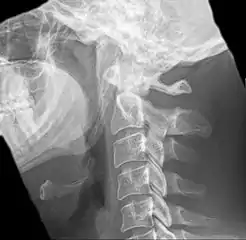

Radiograph, lateral view showing joint-like formation in ossified stylohyoid ligament

Imaging is important and is diagnostic. Visualizing the styloid process on a CT scan with 3D reconstruction is the suggested imaging technique.[12] The enlarged styloid may be visible on an orthopantogram or a lateral soft tissue X ray of the neck.